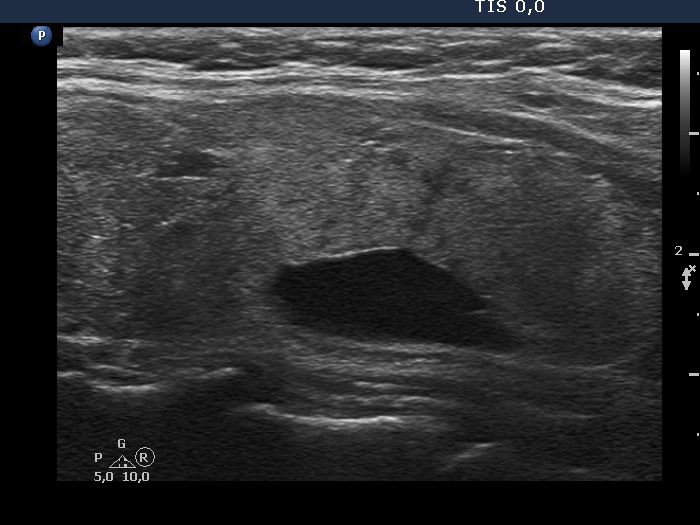

Left lobe, another longitudinal view. The cyst is located dorsal to the thyroid tissue.